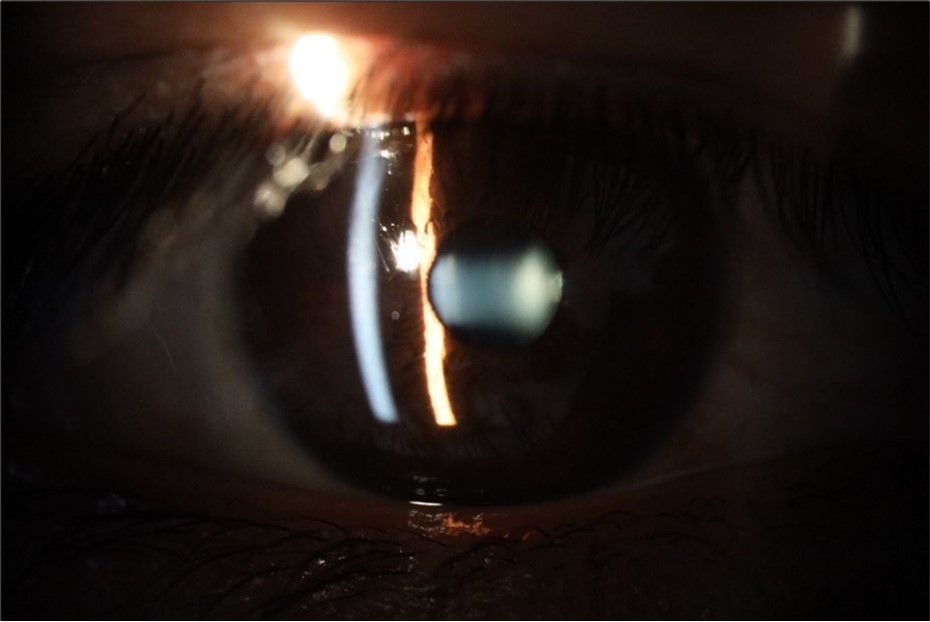

Figure 31.The photograph of the right eye shows an almost normal mirror reflection, as well as a better pupillary dilation.

The photograph of the right eye shows an almost normal mirror reflection, as well as a better pupillary dilation.

Figure 32.The macro photograph of the right eye shows us a cornea, anterior camera, and crystalline lens in very good condition.

The macro photograph of the right eye shows us a cornea, anterior camera, and crystalline lens in very good condition.